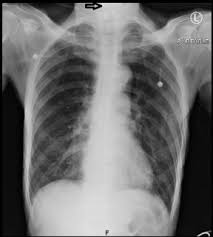

Covid 19 Coronavirus Diagnosis Chest X Ray And Ct Scan from www.verywellhealth.com Throat cancer refers cancer that develops in your throat (pharynx) or voice box (larynx). These are the headlines from several drug leaflets. The cause of the tightness can vary from an infection like strep throat to a more serious allergic. We also look at the various types and the differences between them. When you first hear about a new drug, what would you like to know about it? Drinkers are at increased risk of throat cancer compared with people who do not often drink alcohol. Though most throat cancers involve the same types of cells, specific terms are used to differentiate the part of the throat where cancer originated. Most throat cancers develop in adults older than 50.

Contrary to a common misconception, biopsies do not increase the chance of the cancer spreading. Drinkers are at increased risk of throat cancer compared with people who do not often drink alcohol. Its called throat cancer or lung cancer. Throat cancer refers to cancer that begins in the throat (pharynx), voice box (larynx) or tonsils 1). Medically reviewed by adithya cattamanchi, m.d. It's not a fracture.you see there is no swelling on my leg. Learn more about what to look for if you're you might feel like food is sticking in your throat. Lump or sore that doesn't go away. How many meals a day do you have? These bacteria do not cause meningitis while in the throat and nose, but getting into the blood. After treatment, therapy is needed to. Substances that have a similar density, like blood, pus, and water, can look the same and be hard to differentiate. What throat cancer look like.

Lump or sore that doesn't go away. Do you believe your eating habits to be healthy? Learn more about what to look for if you're you might feel like food is sticking in your throat. They do not have a clear idea as to how throat cancer looks like. Its called throat cancer or lung cancer. What can an xray show? Beams are directed at the tumor and affect only the projection area. A lump in your neck: Does he like his job? Many people mistake throat cancer with cold or sore throat. Throat cancer causes, signs and symptoms. Men are more likely than women to develop the provider may look in your throat or nose using a flexible tube with a small camera at the end. After treatment, therapy is needed to.